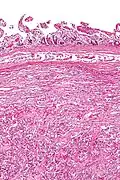

Intermed. mag.

Intermed. mag. -

A gangliocytic paraganglioma is a rare tumour that is typically found in the duodenum and consists of three components: (1) ganglion cells, (2) epithelioid cells (paraganglioma-like) and, (3) spindle cells (schwannoma-like).[1]

GP consist of three components (1) ganglion cells, (2) epithelioid cells (neuroendocrine-like), and (3) spindle cells (schwannoma-like). The microscopic differential diagnosis includes poorly differentiated carcinoma, neuroendocrine tumour and paraganglioma.[1]